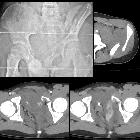

Plain radiograph

X-rays are a quick and simple test that will detect the majority of pelvic fractures. They can be difficult to assess because of the complexity of the shape of the sacrum, pelvis and proximal femora.

CT

CT is the modality of choice for accurately depicting complex acetabular and pelvic ring fractures. After an initial plain radiograph, a CT is often required to make an accurate assessment of the fracture and often aids in surgical decision making.